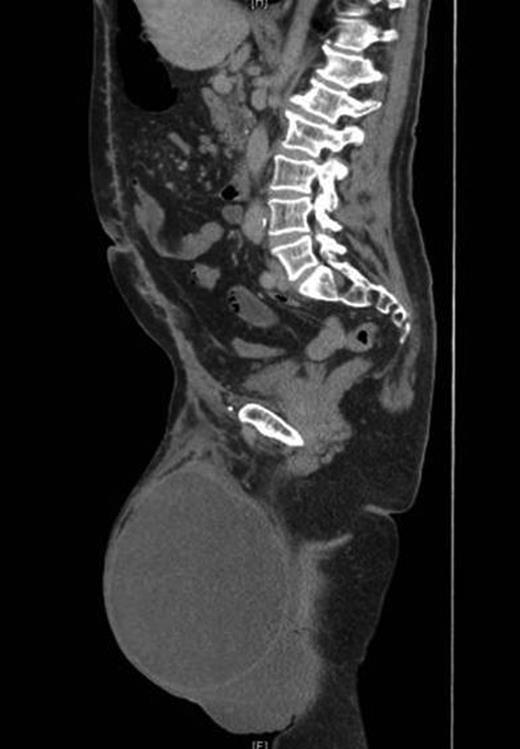

A contrast-enhanced computed tomography (CT) scan revealed the hernia sac containing most of the colon and small bowel with only the rectum, proximal jejunum and duodenum lying within the abdomen (Fig. 2). Preoperative anaesthetic assessment was completed and the patient was admitted to hospital 2 days preoperatively for bowel preparation. After a midline laparotomy, attempts at reduction were not successful even after dividing the inguinal ligament. Reduction in hernia contents was possible only after completely dividing the lower end of the left rectus abdominis muscle. The hernial sac was then dissected and resected. Then, component separation technique was performed laparoscopically using the same balloons used for total extra peritoneal (TEP repair for inguinal hernias). A 2 cm transverse incision located just under the rib cage in the mid-clavicular line was deepened until the area just posterior to the external oblique was entered. The large balloon was inserted in this space in the direction of the pelvis and inflated under laparoscopic guidance to create the space between the external and internal obliques. This was followed by the triangular balloon and insufflation was started at pressure of 11 mmHg under laparoscopic control. A lateral incision to introduce a 5 mm trocar is performed and a pair of laparoscopic scissors introduced to make a longitudinal incision in the external oblique aponeurosis extending along the mid-clavicular line from the rib cage to the inguinal ligament. The same is repeated on the other side. The hernia defect was then repaired extraperitoneally using a large polypropylene mesh extending from the anterior superior iliac spine to the symphysis pubis. Both the inguinal ligament and rectus abdominis muscle were repaired. The procedure ended by mass closure of the laparotomy incision.

On follow-up after 8 weeks, the patient was in a very good general condition with intact hernia repair and laparotomy wound. He was found to have a moderate scrotal swelling (Fig. 3) which proved by CT scan to be a postoperative seroma (Fig. 4) which was managed conservatively.

Postoperative CT scan showing intact repair and clear fluid in the scrotum.